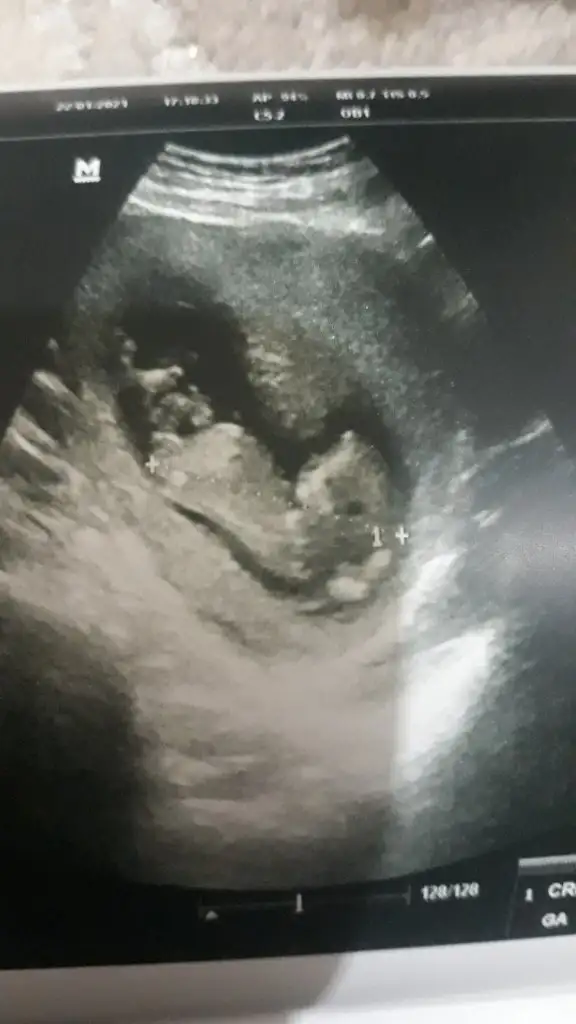

Ikra meyra Ikra meyra canim meraba 12+1 doktorum %80 tahminde bulundu ama sana da sormak istedim bi bakarmisin şimdiden tsk ederim 😇🥰

13 hafta USG olursa paylaşın ilk bebekmi net usg olsa net tahmin ederim kesin kız yada erkek derdim canım

Bana da yorum yapabilirsiniz 12+4